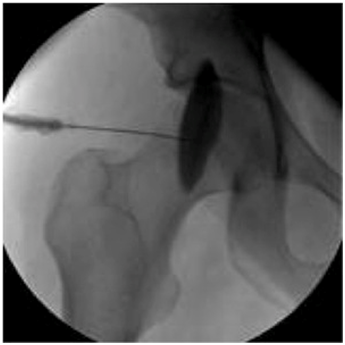

But steroid injection with imaging guide like X ray or CT scan or ultrasound at the usual levels which is the lesser trochanter or at muscular tendons junction and usually radio opaque substance is used for accuracy. The level of injection can be at lesser trochanteric level as the iliopsoas tendon attached to it or at the level of acetabulum (in cases of metal friction as a cause of iliopsoas tendonitis). This could be used to confirm the diagnosis and/or apply as a treatment.1 (Figure 3).

Figure 3 Iliopsoas tendonitis injection.